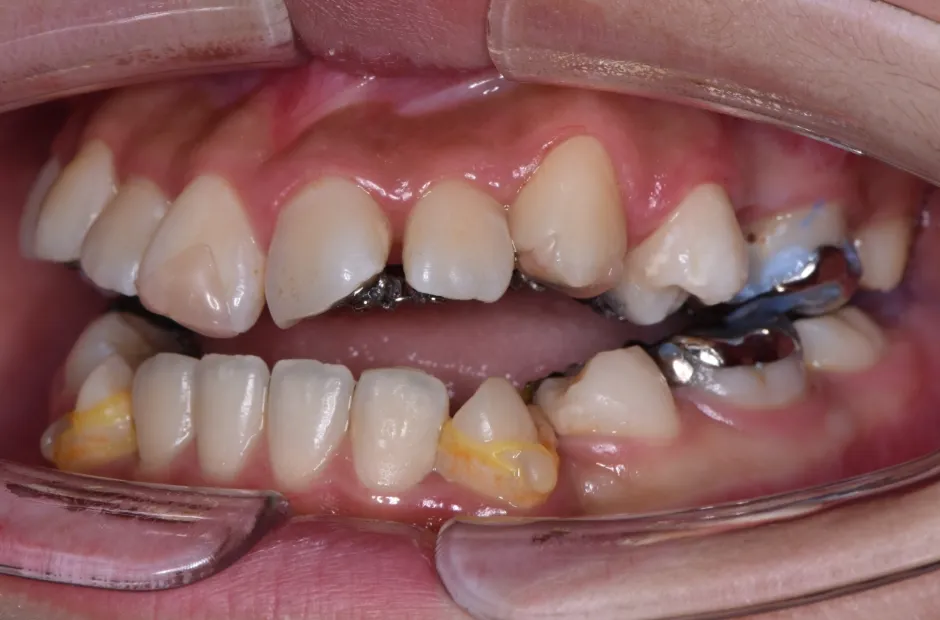

治療症例

ブラケット矯正

前歯部反対咬合

| 診断名・主訴 | 前歯部反対咬合 |

|---|---|

| 年齢・性別 | 14歳・男性 |

| 治療期間・回数 | 1年2か月 |

| 治療に用いた主な装置 | ブラケット矯正 |

| 抜歯部位 | なし |

| 治療費 | 60万円(税抜) |

| リスク・副作用 | 装置による違和感・疼痛・歯肉退縮・歯根吸収・虫歯のリスクなど |

治療前

治療中

治療後